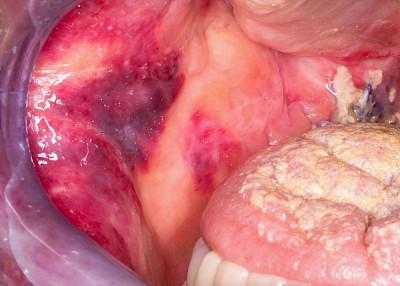

Einbiss & Bluterguss

Blutungen & Blutergüsse sind in den meisten Fälllen als ein Zeichen einer Verletzung wie z.B. einem Einbiss oder nach einem Sturz zu werten.

Blutpunkte (z.B. Petechien), Blutblasen (z.B. Hämangiome) & rote Flecken (z.B. Ausschlag) haben in der Regel eine längere Entstehungsgeschichte und sind häufig nicht auf eine direkte kurzzeitig zurückliegende Verletzung zurückzuführen.